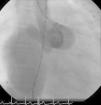

Regular follow-up was performed and transthoracic echocardiography detected a residual shunt at the distal extremity of the fistula. One year after the first intervention, angiography was repeated and two small orifices were clearly seen in the extremity where the fistula drained into the right atrium. Percutaneous closure of these orifices was attempted. A 6 Fr venous sheath and a 6 Fr arterial sheath were used through a femoral approach. Two guide wires were advanced from the aortic end to the atrial end, one through each orifice, and two arteriovenous loops were created. Two 6 Fr Concierge Amplatz Left 2 guiding catheters were introduced in the distal extremity of the fistula. An 8/6 mm Amplatzer® duct occluder (AGA Medical) was deployed through the atrial end to close the lower orifice (Figure 3). The upper orifice was left open, due to dislocation and instability in the position of the guiding catheter in the distal part of the fistula, and the long duration of the procedure. Control angiography showed a residual shunt through the upper orifice.